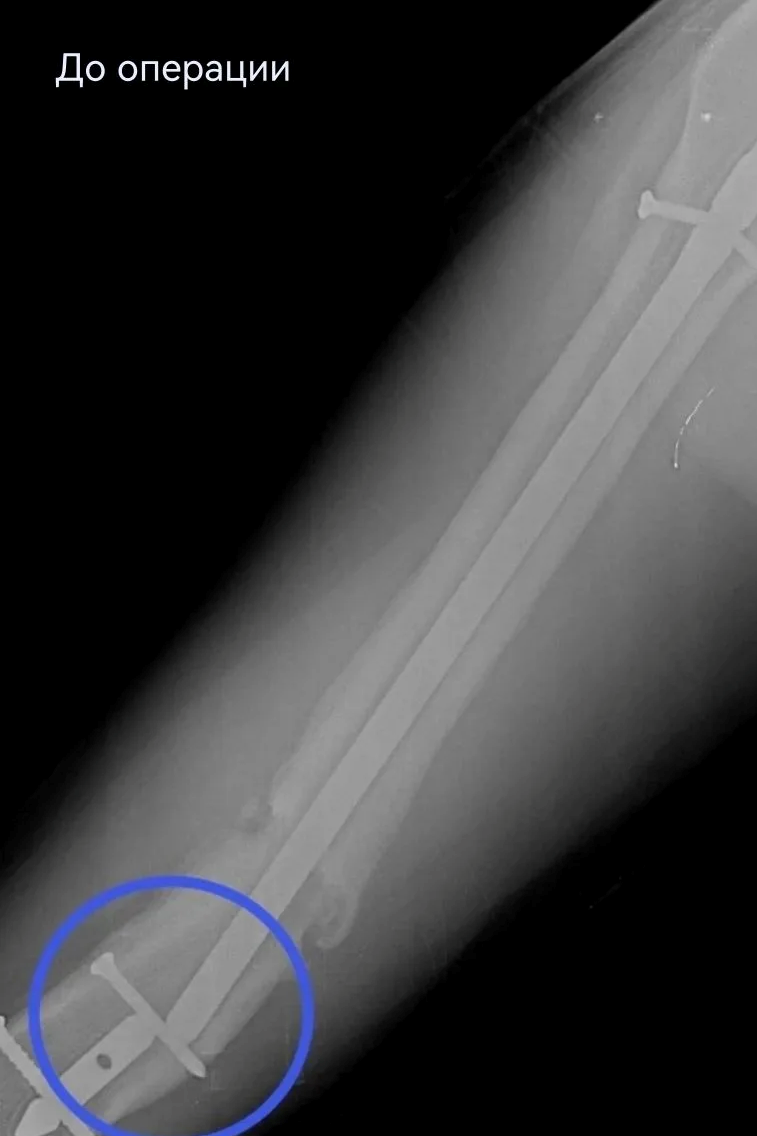

17‑летний Николай поступил с осложнением после операции по поводу перелома бедра. Ранее ему был установлен интрамедуллярный штифт – для фиксации отломков кости с возможностью ранней нагрузки на конечность. Но прежде, чем перелом консолидировался, штифт сломался. Врачам нужно было найти новое, более подходящее решение, при этом избежать травматичного открытого доступа и обойтись без больших разрезов. Задачу усложнял сломанный внутри кости штифт. Специального серийного устройства для его удаления малоинвазивным способом не существует. Чтобы пройти 40 сантиметров по костномозговому каналу, захватить и извлечь фиксатор, сургутские специалисты создали свою систему на базе имеющего набора проводников и экстракторов. Тщательное предоперационное планирование принесло желаемый результат в ходе вмешательства.

После успешного удаления прежней конструкции пациенту установили новую надежную систему - с учётом предыдущего опыта. Для этого понадобилось несколько небольших разрезов (не более 2 см). На второй день после операции Николай передвигался по отделению с помощью костылей, уже нагружая оперированную конечность. Сейчас он внимательнее прислушивается к рекомендациям, от выполнения которых зависит благополучие восстановительного периода.